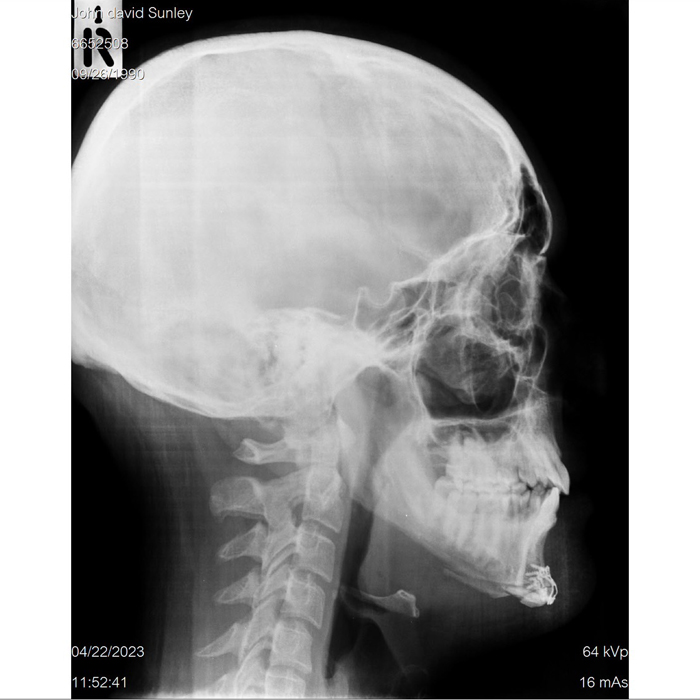

![]() |

| Before | After |